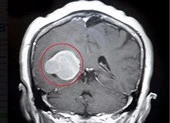

Sau khi làm một loạt kiểm tra tiêu chuẩn, ông được đưa vào quét CT. Bản chụp khiến mọi người kinh ngạc khi thấy ông có một vùng đen chừng 9 cm trông giống như khoảng trống phía sau trán.

Bản quét MRI sau đó xác nhận khoảng đen kia chính là khối khí rỗng trong phần thùy trán phải. Khối khí được tạo thành do một khối u não lành tính đã "ăn" mất một phần hộp sọ bệnh nhân. Đây là phần não liên quan đến chức năng vận động, giải quyết vấn đề, trí nhớ, ngôn ngữ, hành vi xã hội và tình dục.

Khối khí được các bác sĩ gọi là pneumatocele. Tình trạng này thường hay xảy ra ở người bị thương trên mặt, nhiễm trùng xoang, phẫu thuật lấy khối u não. Mặc dù có thể phẫu thuật để khối khí này thoát ra khỏi não bệnh nhân nhưng nó cũng ẩn chứa nhiều nguy cơ.  Vì tuổi đã cao, cụ ông quyết định không phẫu thuật, thay vào đó được chữa trị bằng để giảm nguy cơ đột quỵ.